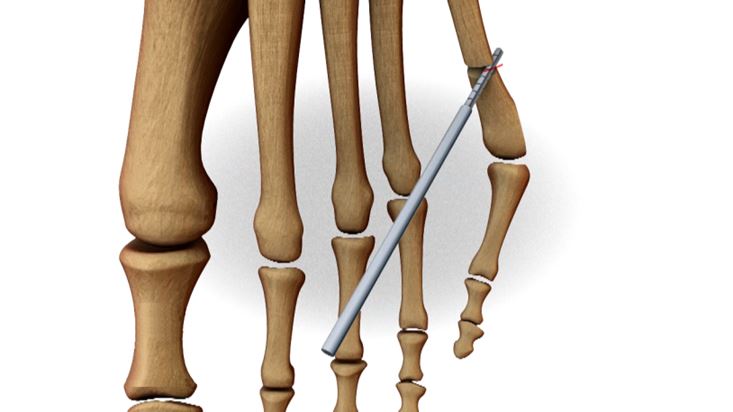

De belangrijkste behandeling bestaat uit goed schoeisel eventueel aangevuld met steunzolen. Bij ernstige pijnklachten of last kan een ingreep wenselijk zijn. Via een incisie van 2 à 3 mm brengen we een klein boortje in. We zagen hiermee een middenvoetsbeentje door, om de voet wat smaller te maken.

Op die manier verdwijnt de uitstekende pijnlijke knobbel.